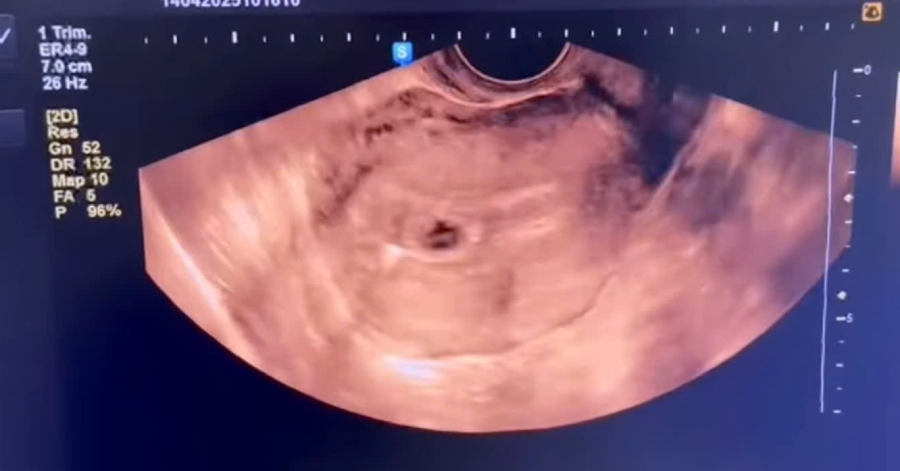

Bệnh nhân N.T.G (21 tuổi) bị đột quỵ nhồi máu não được đưa đến điều trị trong thời gian vàng. Anh G. có tiền sử hút thuốc lá từ năm 16 tuổi, trung bình mỗi ngày hút từ 1-2 gói. Khi bác sĩ thông báo, bệnh nhân và gia đình đều sốc vì anh G. đang ở tuổi thanh niên.

Bác sĩ Cường cho rằng, đột quỵ có thể xuất hiện dấu hiệu cảnh báo hoặc không. Người có nguy cơ có thể tầm soát đột quỵ bằng kiểm tra mạch máu não, các yếu tố bệnh nền đi kèm.